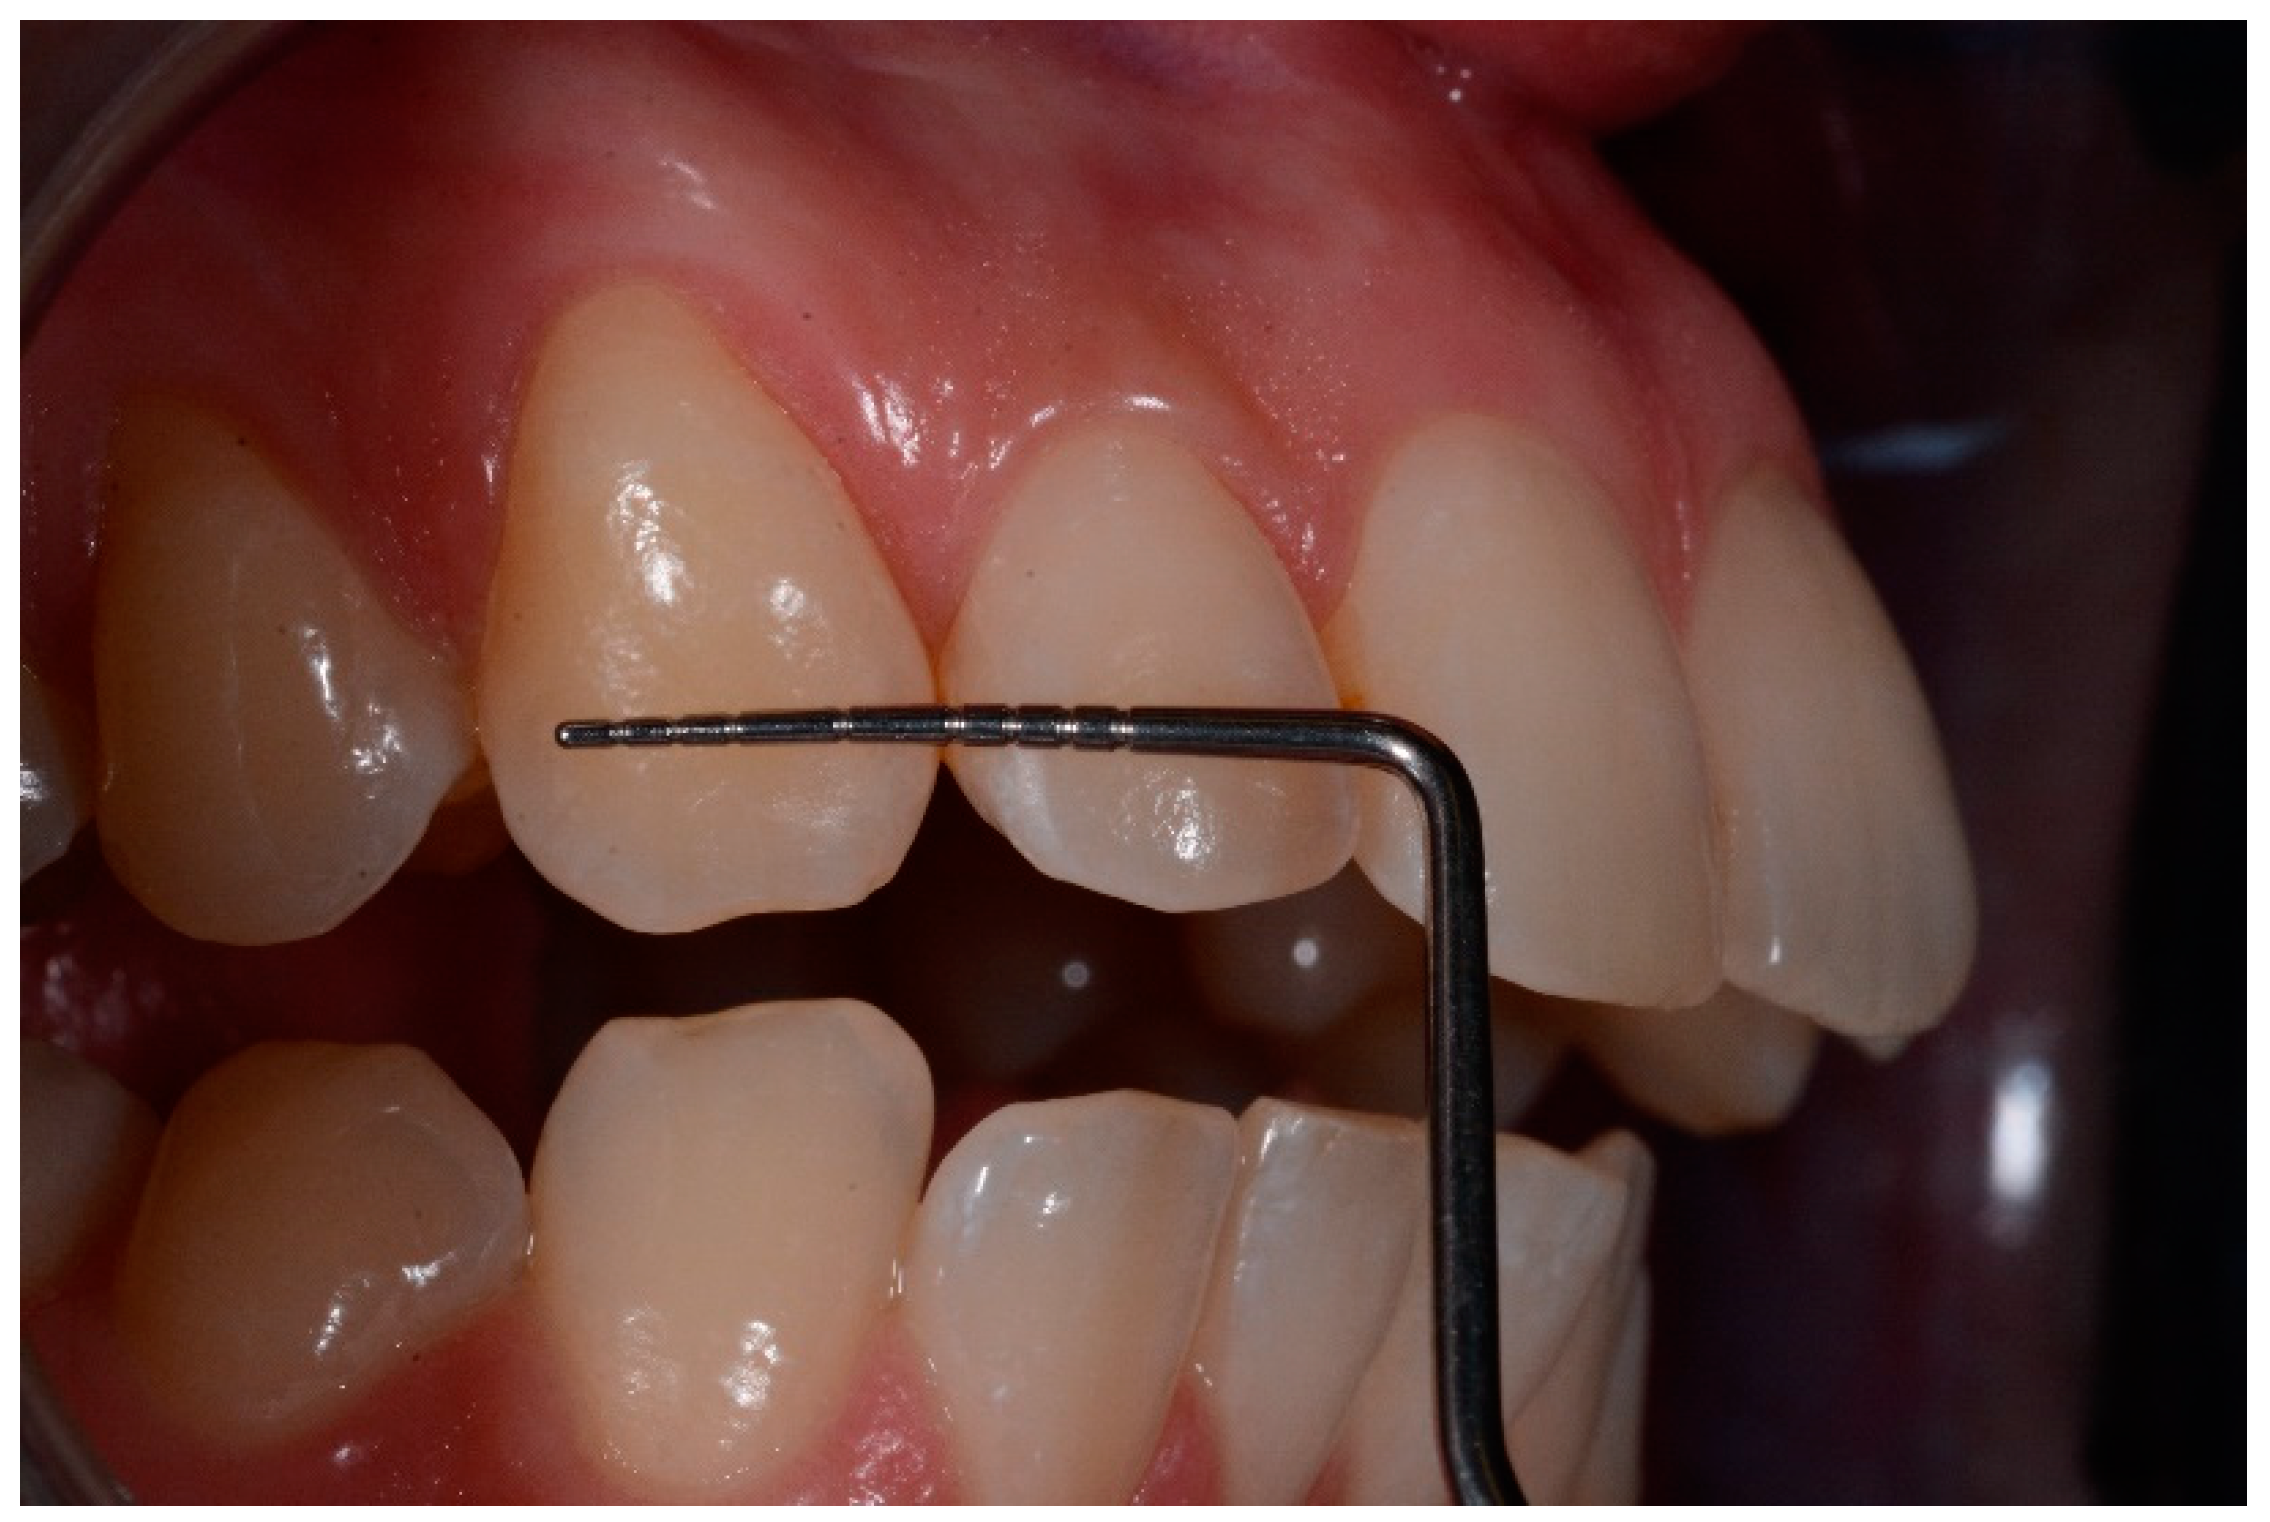

- application of 99% pure ethanol (Icon-Dry, DMG) for 30 s; (Figure 1)

- assessment of needing for further etching cycles by the operator